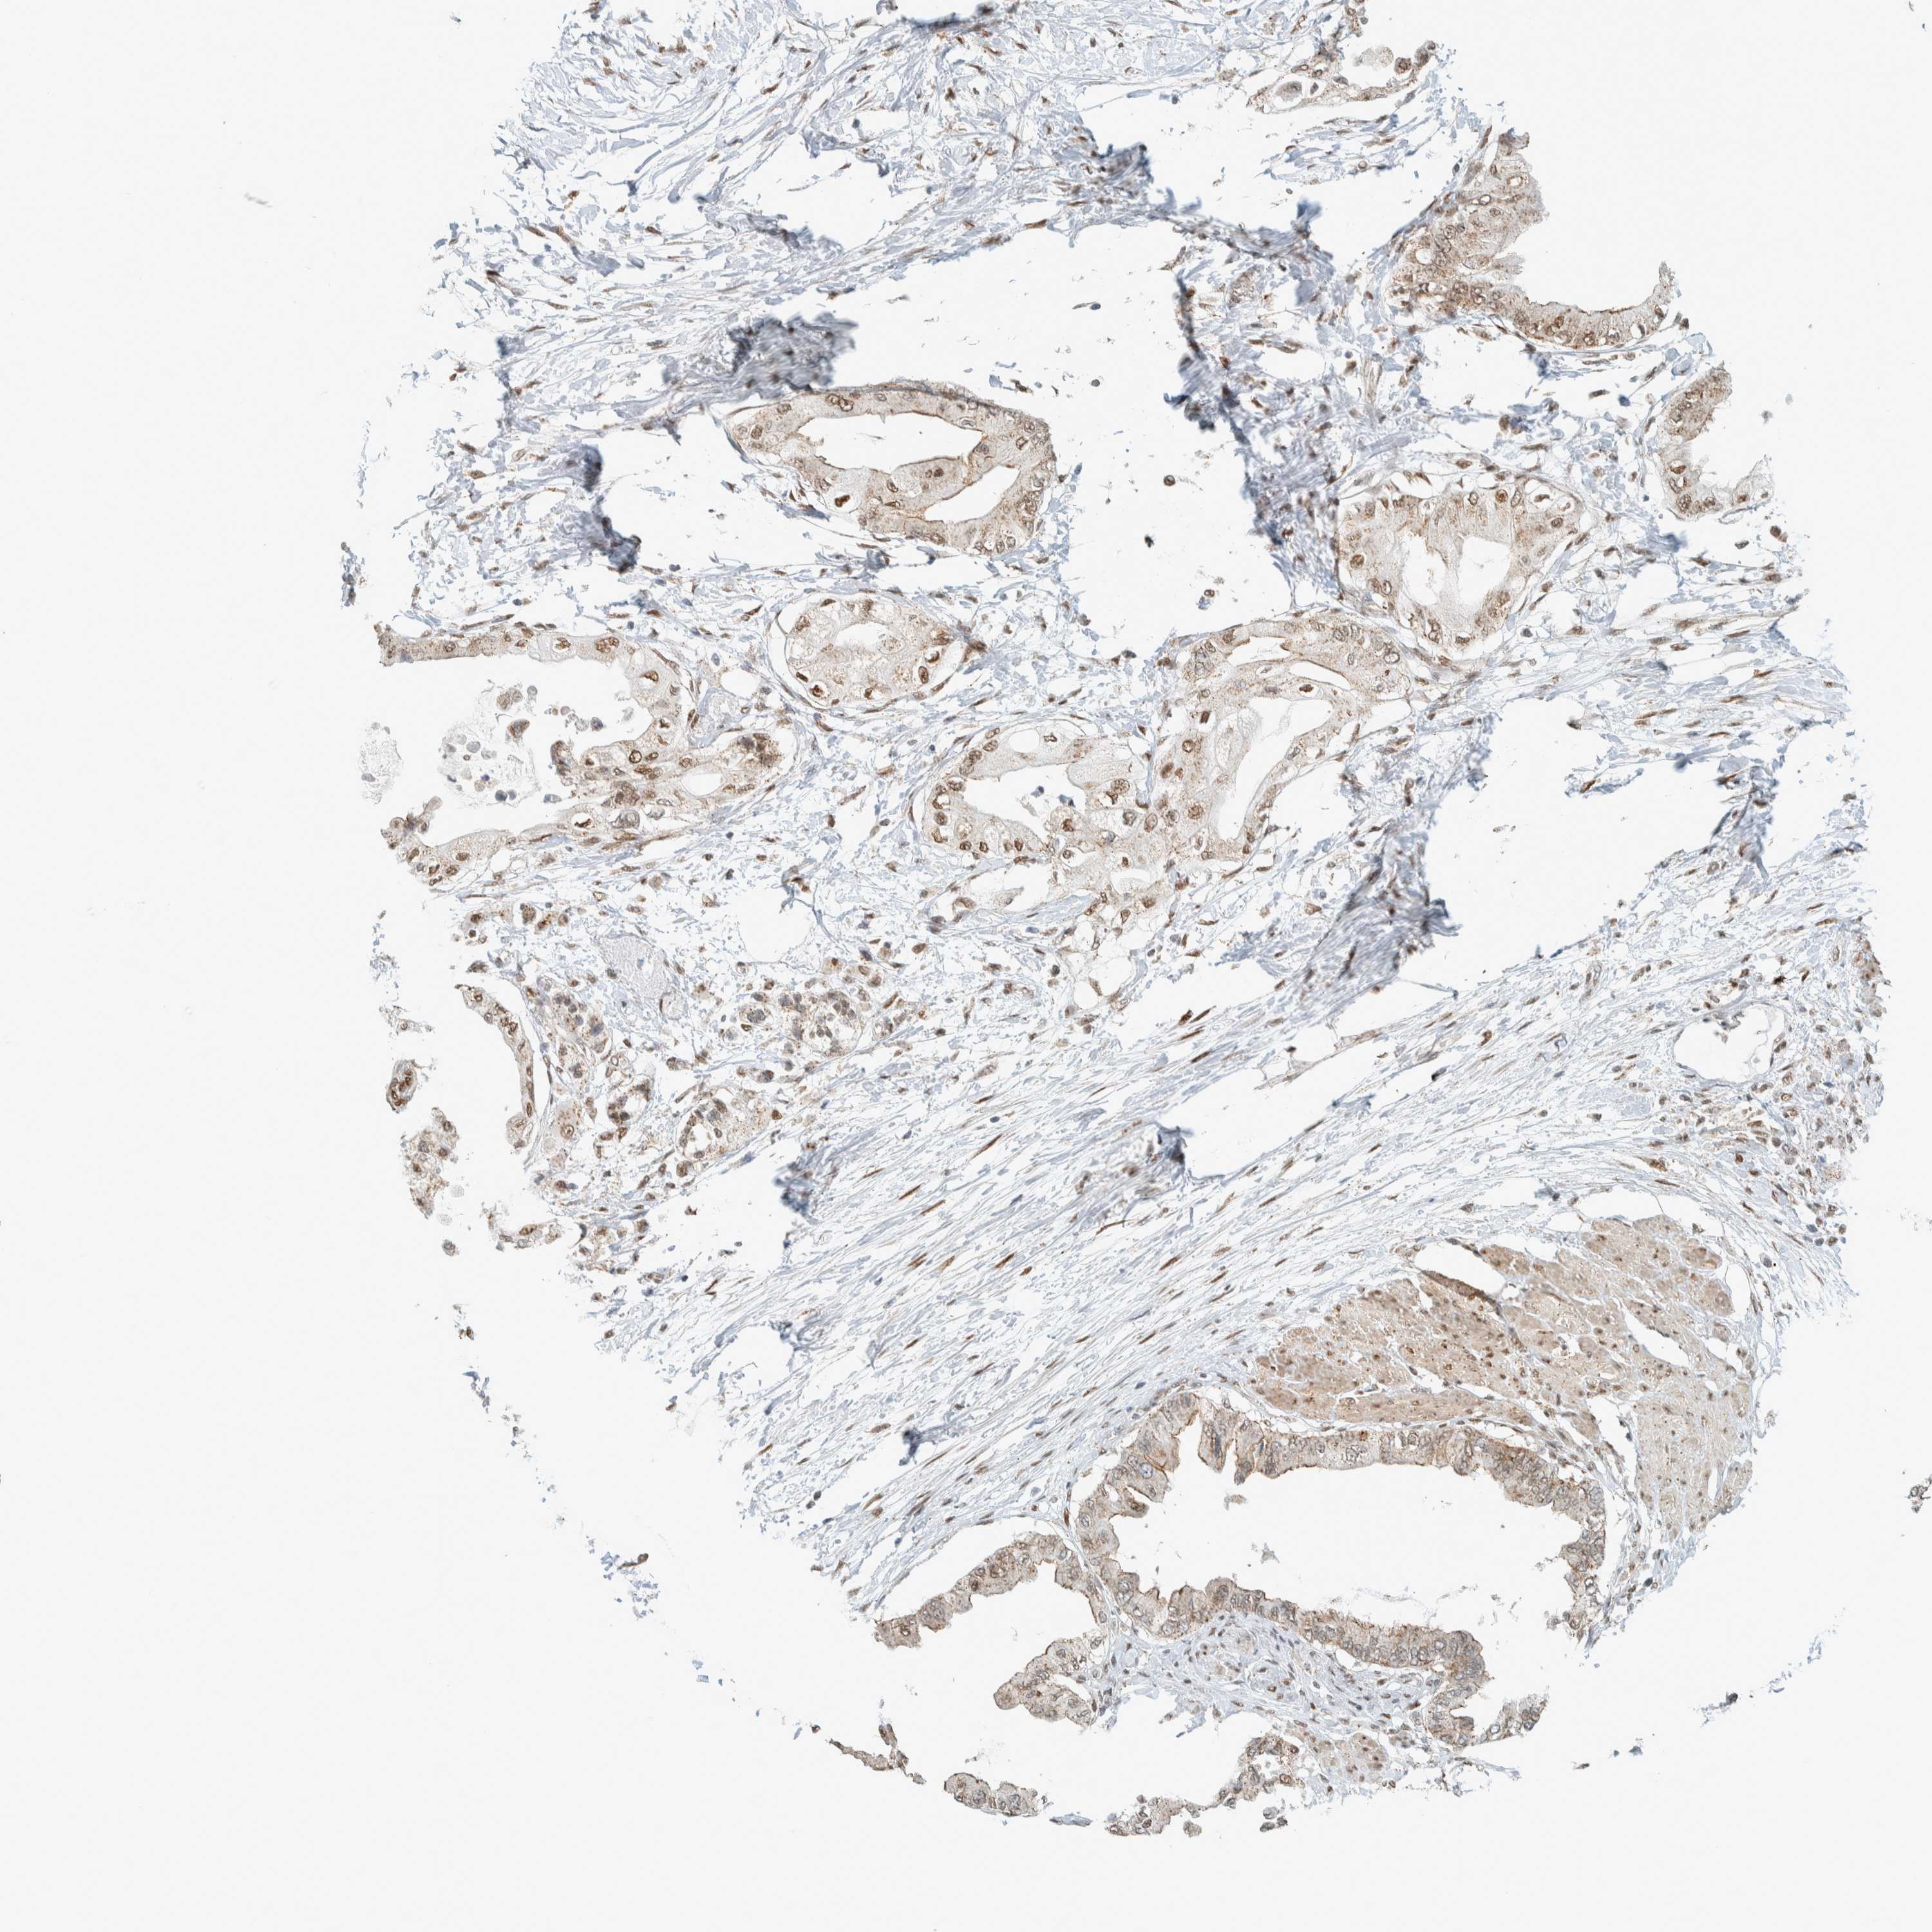

PANCREATIC CANCER - Protein expressioni

A mouse-over function shows sample information and annotation data. Click on an image to view it in a full screen mode. Samples can be filtered based on level of antibody staining by selecting one or several of the following categories: high, medium, low and not detected. The assay and annotation is described here.

Note that samples used for immunohistochemistry by the Human Protein Atlas do not correspond to samples in the TCGA dataset.

Antibody stainingi

Antibody staining in the annotated cell types in the current human tissue is reported as not detected, low, medium, or high, based on conventional immunohistochemistry profiling in selected tissues. This score is based on the combination of the staining intensity and fraction of stained cells.

Each image is clickable and will lead to virtual microscopy that enables deeper exploration of all samples and also displays staining intensity scores, fraction scores and subcellular localization as well as patient and tissue information for each sample.

Antibody HPA023881

Staining

High

Medium

Low

Not detected

Intensity

Strong

Moderate

Weak

Negative

Quantity

>75%

75%-25%

<25%

None

Location

Nuclear

Cytoplasmic/membranous

Cytoplasmic/membranous,nuclear

Adenocarcinoma, NOS